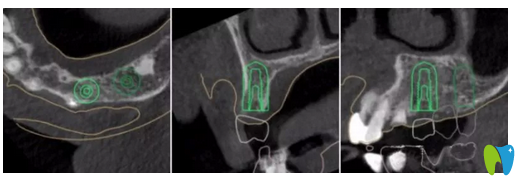

CT片顯示14區(qū)缺牙間隙較狹窄

CBCT顯示:14區(qū)缺牙間隙較狹窄,模擬植入后,近遠(yuǎn)中距臨牙安 全距離不足1.5mm;其余缺牙區(qū)骨質(zhì)及骨量的情況,以及距離上頜竇底高度均基本滿足種植要求。缺牙區(qū)咬合高度基本滿足后期修復(fù)要求。

▲ 患者左上6牙位模擬種植圖

▲ 患者左上4牙位模擬種植圖